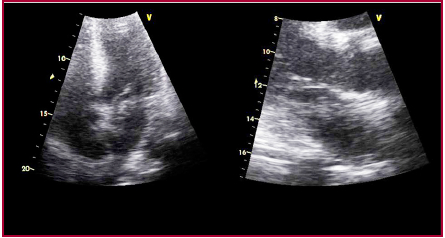

Evolucionó sin complicaciones durante las primeras 72 horas; al cuarto día posterior a la maniobra de valsalva, tuvo unrecurrenciaa recurrencia con un paro cardiorrespiratorio con disociación electromecánica. Se le realizaron maniobras de reanimación cardiopulmonar exitosas, intubación orotraqueal y conexión a asistencia respiratoria mecánica. No presentó shock. Se le realizó un ecocardiograma de urgencia que evidenció una imagen móvil, de aspecto trombótico, que se encontraba cabalgando entre ambas aurículas a través de un foramen oval permeable, en contacto tanto con el tracto de entrada del VD como del ventrículo derecho (VI).